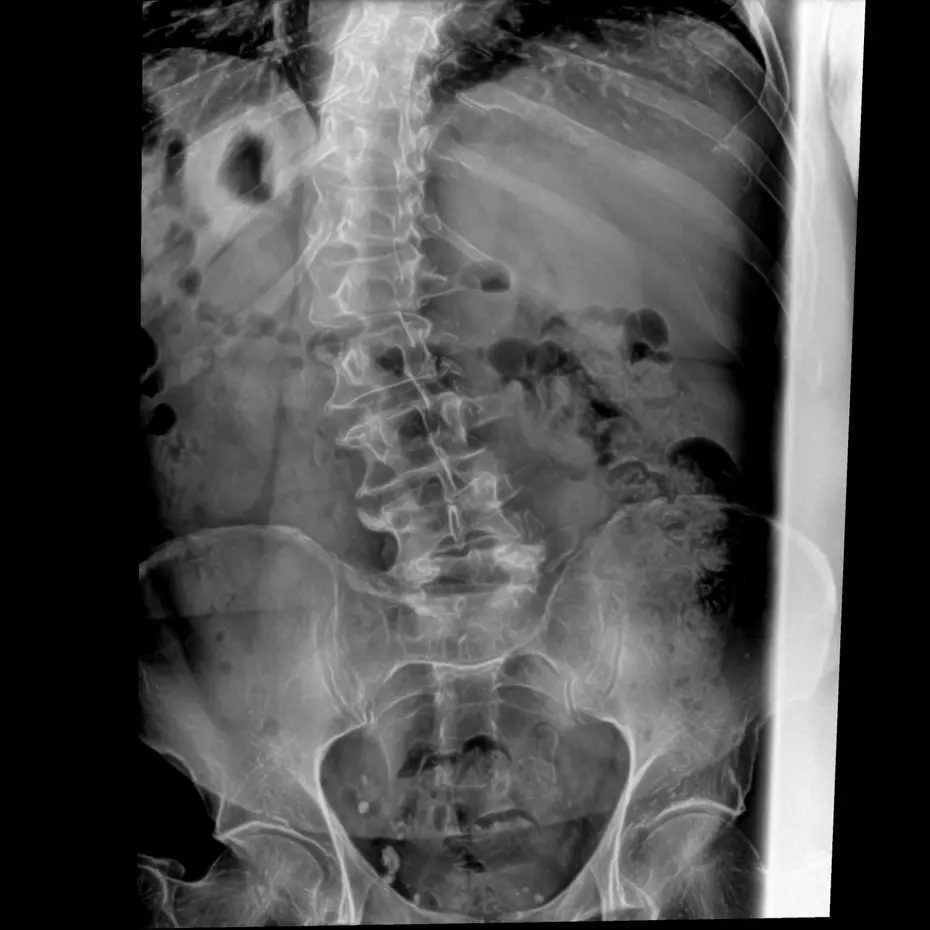

During his Army physical was the first time he heard about scoliosis. When his lower back was finally x-rayed in chiropractic school the extent of the curvature and unevenness of his spine was seen for the 1st time.